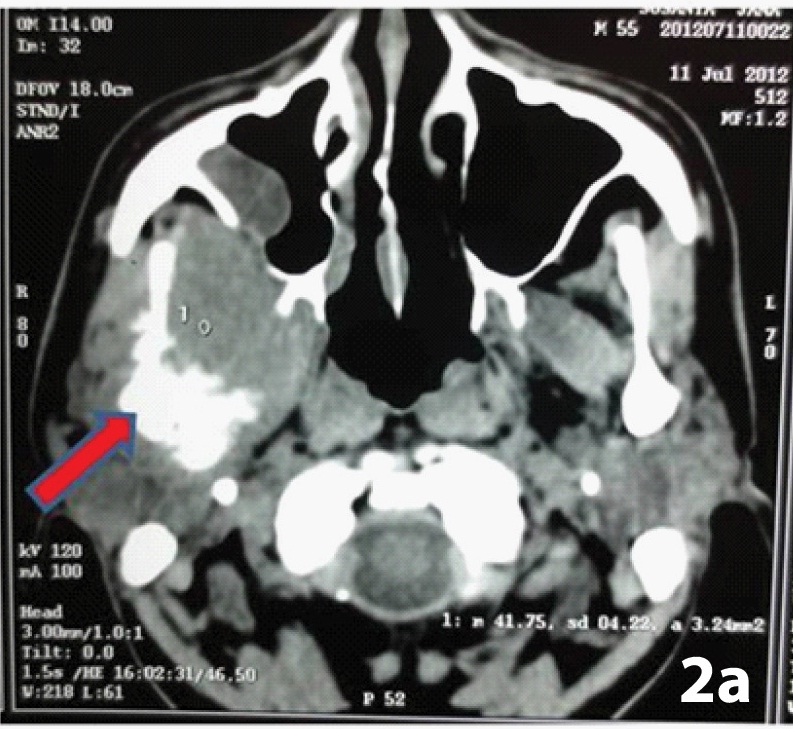

Coronal and axial CT scan revealed an ill defined osseous outgrowth arising from right condyle of mandible showing bony destruction and deformity with soft tissue component and islands of amorphous calcification. The cortex of the lesion was seen destroyed, continuous with that of underlying bone from which it arose and the trabecular pattern was seen merging into the medullary cavity [Table/Fig-2a,b]. The lesion involved the right infratemporal fossa, masticator space and eroded the posterior wall of the maxillary sinus. Such findings of a destructive lytic lesion that too of a short duration favored an underlying malignant process like osteosarcoma, chondrosarcoma or any metastatic tumour of TMJ. Fine needle aspiration cytology of the mass was performed which was non contributory. An incisional biopsy revealed neoplastic chondrocytes in lacunar spaces present in a chondroid matrix, exhibiting pleomorphic and hyper chromatic nucleus. A diagnosis of chondrosarcoma (CS) was made but possibility of chondroblastic osteosarcoma was kept in mind as it was a small biopsy specimen. Investigations like chest radiographs, ultrasound of neck and abdomen and CT of neck were done to rule out metastasis. Segmental resection of ramus was done along with excision of tumour mass that measured about 10 x7 cm. The condyle was resorbed and cut surface of tumour was whitish opaque, peripherally slightly mucoid and with central foci of calcifications [Table/Fig-3a,b]. Microscopically the sections showed typical low grade cartilaginous matrix and pleomorphic chondrocytes in large lacuna with hyperchromatic nuclei and open chromatin pattern, arranged in a lobular configuration. This sharply contrasted the adjacent foci made of pleomorphic spindle cells in storiform pattern [Table/Fig-4a,b]. There were foci of enchondral ossification. No presence of tumour osteoid could be discerned in multiple, serial sections. A final diagnosis of dedifferentiated chondrosarcoma of right TMJ was made. The surgical margins of resected specimen were free of tumour infiltration. On advice of the medical oncologist, the patient received radiotherapy one month post- operatively and remained in a one year disease free follow-up.

Axial view showing condylar erosion with trabecular pattern continuous with the medullary cavity (arrow)